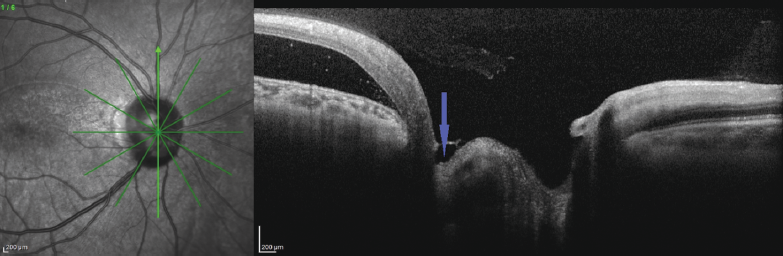

In the study of the ONH area from the temporal side, a relationship of NED with the ONH structures was found; in the same area, the intravagination of the retinal nerve fiber layer (RNFL) into the ONH structure was observed that enabled us to confirm the diagnosis of optic disk pit (Fig. 6).

Fig. 6. OCT of patient B. Radial scan across the optic disc cup center (arrow – connection of neuroepithelium detachment with optic disc structures)

Рис. 6. ОКТ пациентки Б. Радиальный срез через центр экскавации диска зрительного нерва (стрелка — связь отслойки нейроэпителия со структурами диска зрительного нерва)